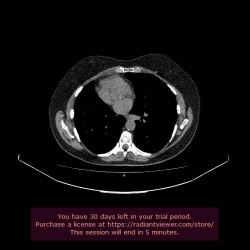

Добрый день. Исследование выполнялось на предмет поражения мочеточников после гистерэктомии.

Образование в хвосте поджелудочной железы как находка, при распросе есть жалобы на периодические боли в...